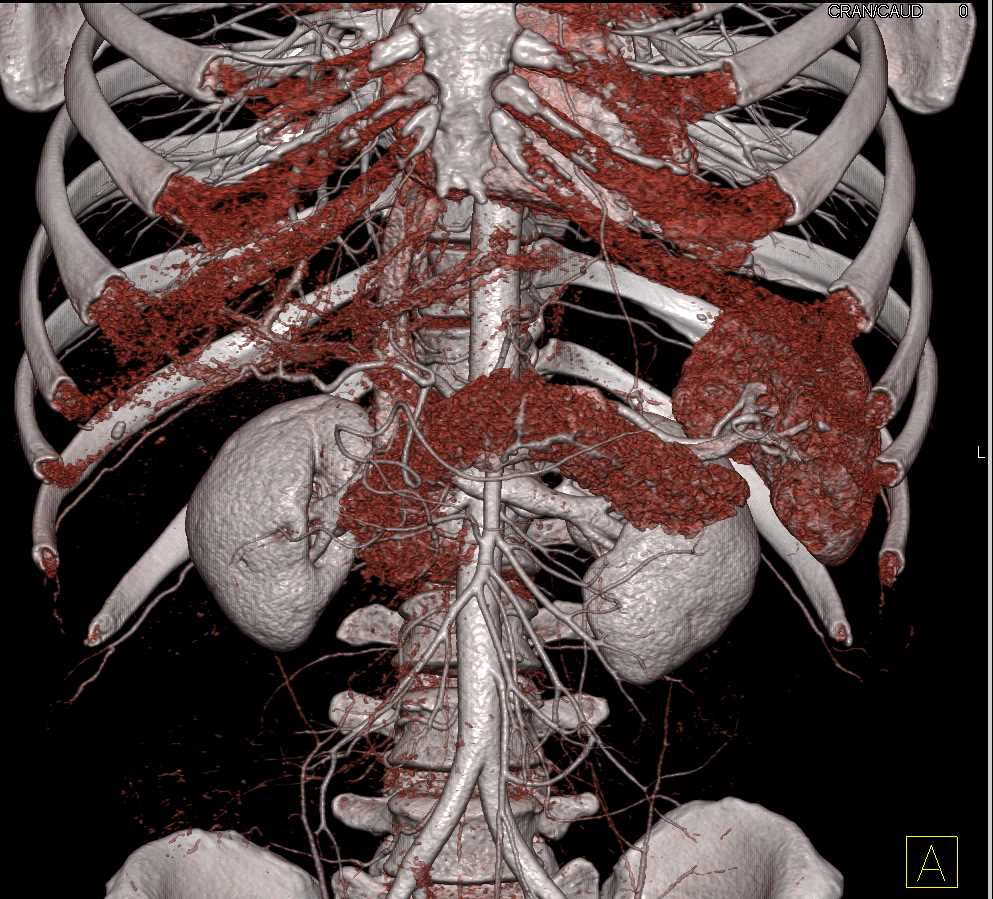

Neuroendocrine Tumor Body of Pancreas